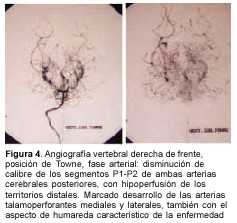

Hasta el advenimiento de las nuevas técnicas de angiorresonancia, el diagnóstico definitivo se hacía exclusivamente con la arteriografía cerebral. Esta es de utilidad para definir la topografía y extensión de las oclusiones. Los hallazgos angiográficos se caracterizan por lesiones que afectan predominantemente la circulación anterior, y que son: en la fase temprana del estudio, disminución del calibre de las carótidas internas intracranealas y del sector proximal de los vasos del círculo de Willis, y desarrollo de colaterales lenticuloestriadas y talamoperforantes ("vasos de moyamoya"). En la fase intermedia la imagen de "nube" o "humareda". Y en la fase tardía el desarrollo de colaterales transóseas y transdurales. El desarrollo de todas estas colaterales es consecuencia de la oclusión carotídea.

A los 3 meses de edad consultó por hemiplejia izquierda y retraso psicomotor. La tomografía computada (TC) de cráneo demostró un infarto hemisférico derecho (figura 1). Los estudios complementarios pusieron de manifiesto una coartación de aorta torácica descendente, sin evidencia de patología arterial sistémica. A nivel encefálico se estudió con angiografía de cuatro vasos de cuello, que demostró la existencia de una enfermedad de moyamoya (figuras 2 a 4). En ese momento no se consideró el tratamiento quirúrgico y una vez estabilizada se otorgó el alta. La coartación de la aorta no requirió cirugía y no se investigó el eventual nexo con la enfermedad de moyamoya. A los 8 meses de edad comenzó con hemiparesia derecha progresiva, lo que junto a su hemiplejia izquierda agravó su déficit motor severamente. Ingresó al Centro Hospitalario Pereira Rossell a los 10 meses. El examen del ingreso mostraba retardo neuropsíquico, hemiplejia izquierda espástica y hemiparesia derecha severa, que apenas vencía gravedad y no oponía resistencia. Una nueva TC mostró como elemento agregado al infarto derecho previo, una isquemia hemisférica izquierda (figura 5). Se resolvió realizar una revascularización quirúrgica del hemisferio izquierdo. Se intervino (figura 6) en el Servicio de Neurocirugía Pediátrica del Hospital. El procedimiento realizado fue una pialsinangiosis, con disección de la arteria temporal superficial izquierda con galea satélite y la sutura del tejido periarterial a la aracnoides temporal. La evolución posoperatoria fue buena, con recuperación progresiva de la función motora del hemicuerpo derecho. En forma gradual también comenzó a recuperar motricidad de su hemicuerpo izquierdo, anteriormente pléjico, y a mejorar sus performances, comenzando a pronunciar palabras a los cuatro meses, aunque manteniendo un retraso en el desarrollo psicomotor. Al año de operada se constató leve hemiparesia izquierda, ausencia de elementos deficitarios motores a derecha y persistencia de alteraciones en el lenguaje. Una ARM realizada a los diez meses de la operación mostró desarrollo de circulación colateral hacia el área quirúrgica (figura 7). Una TC de control permitió ver el infarto secuelar de hemisferio derecho y disminución franca de la hipodensidad del hemisferio izquierdo a los 18 meses de operada (figuras 8 y 9).

En una primera etapa, a los 3 meses de edad, la paciente fue encarada como un stroke en el lactante, y fue estudiada en ese sentido. Se fueron descartando las causas habituales hasta que se llegó al diagnóstico de enfermedad o síndrome de moyamoya con la angiografía. De acuerdo con las normas diagnósticas del cuadro 1, el caso debía ser catalogado como definitivo por la presencia de los ítems A y C. En ese momento no se consideró oportuno el tratamiento quirúrgico.